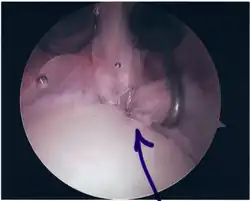

Surgical treatment of SLAP tears has become more common in recent years. The success rate for repairing isolated SLAP tears is reported between 74-94%.[10] While surgery can be performed as a traditional open procedure, an arthroscopic technique[11] is currently favored being less intrusive with low chance of iatrogenic infection.[12]

Following inspection and determination of the extent of injury, the basic labrum repair is as follows.

- The glenoid and labrum are roughened to increase contact surface area and promote re-growth.

- Locations for the bone anchors are selected based on number and severity of tear. A severe tear involving both SLAP and Bankart lesions may require seven anchors. Simple tears may only require one.

- The glenoid is drilled for the anchor implantation.

- Anchors are inserted in the glenoid.

- The suture component of the implant is tied through the labrum and knotted such that the labrum is in tight contact with the glenoid surface.